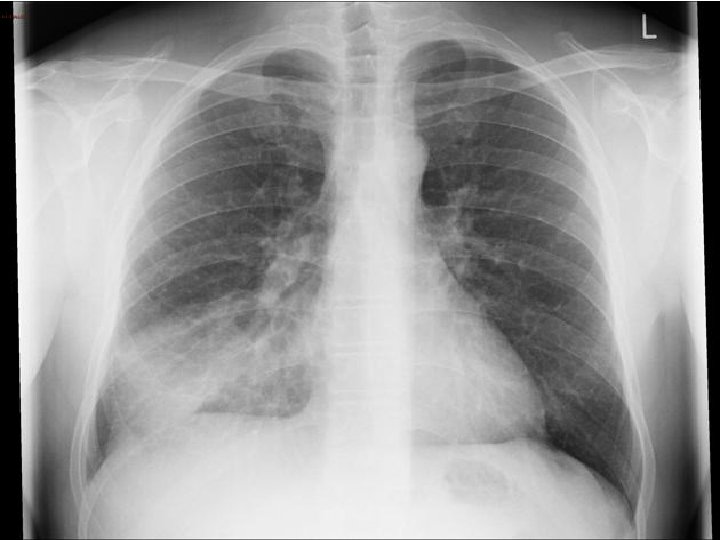

News 0 GCS 14/15 (E 4 V 5 M 6) Difficult exam – moving all 4 limbs equally PERL, Planters normal Examination CVS: Normal RS: Creps right base What else do you want to do?

WCC 14, CRP 180 Na 128(135) Urea 10(6) Investigation Creat 140(60) Ca 2+/TFT/Folate/Vitamin B 12 normal ECG: NSR

CAP – CURB 65 = 3 AKI Diagnosis Multifactorial Hyperactive delirium CAP AKI Drugs (Gabapentin/Co-codamol/Steroids) Change in environment